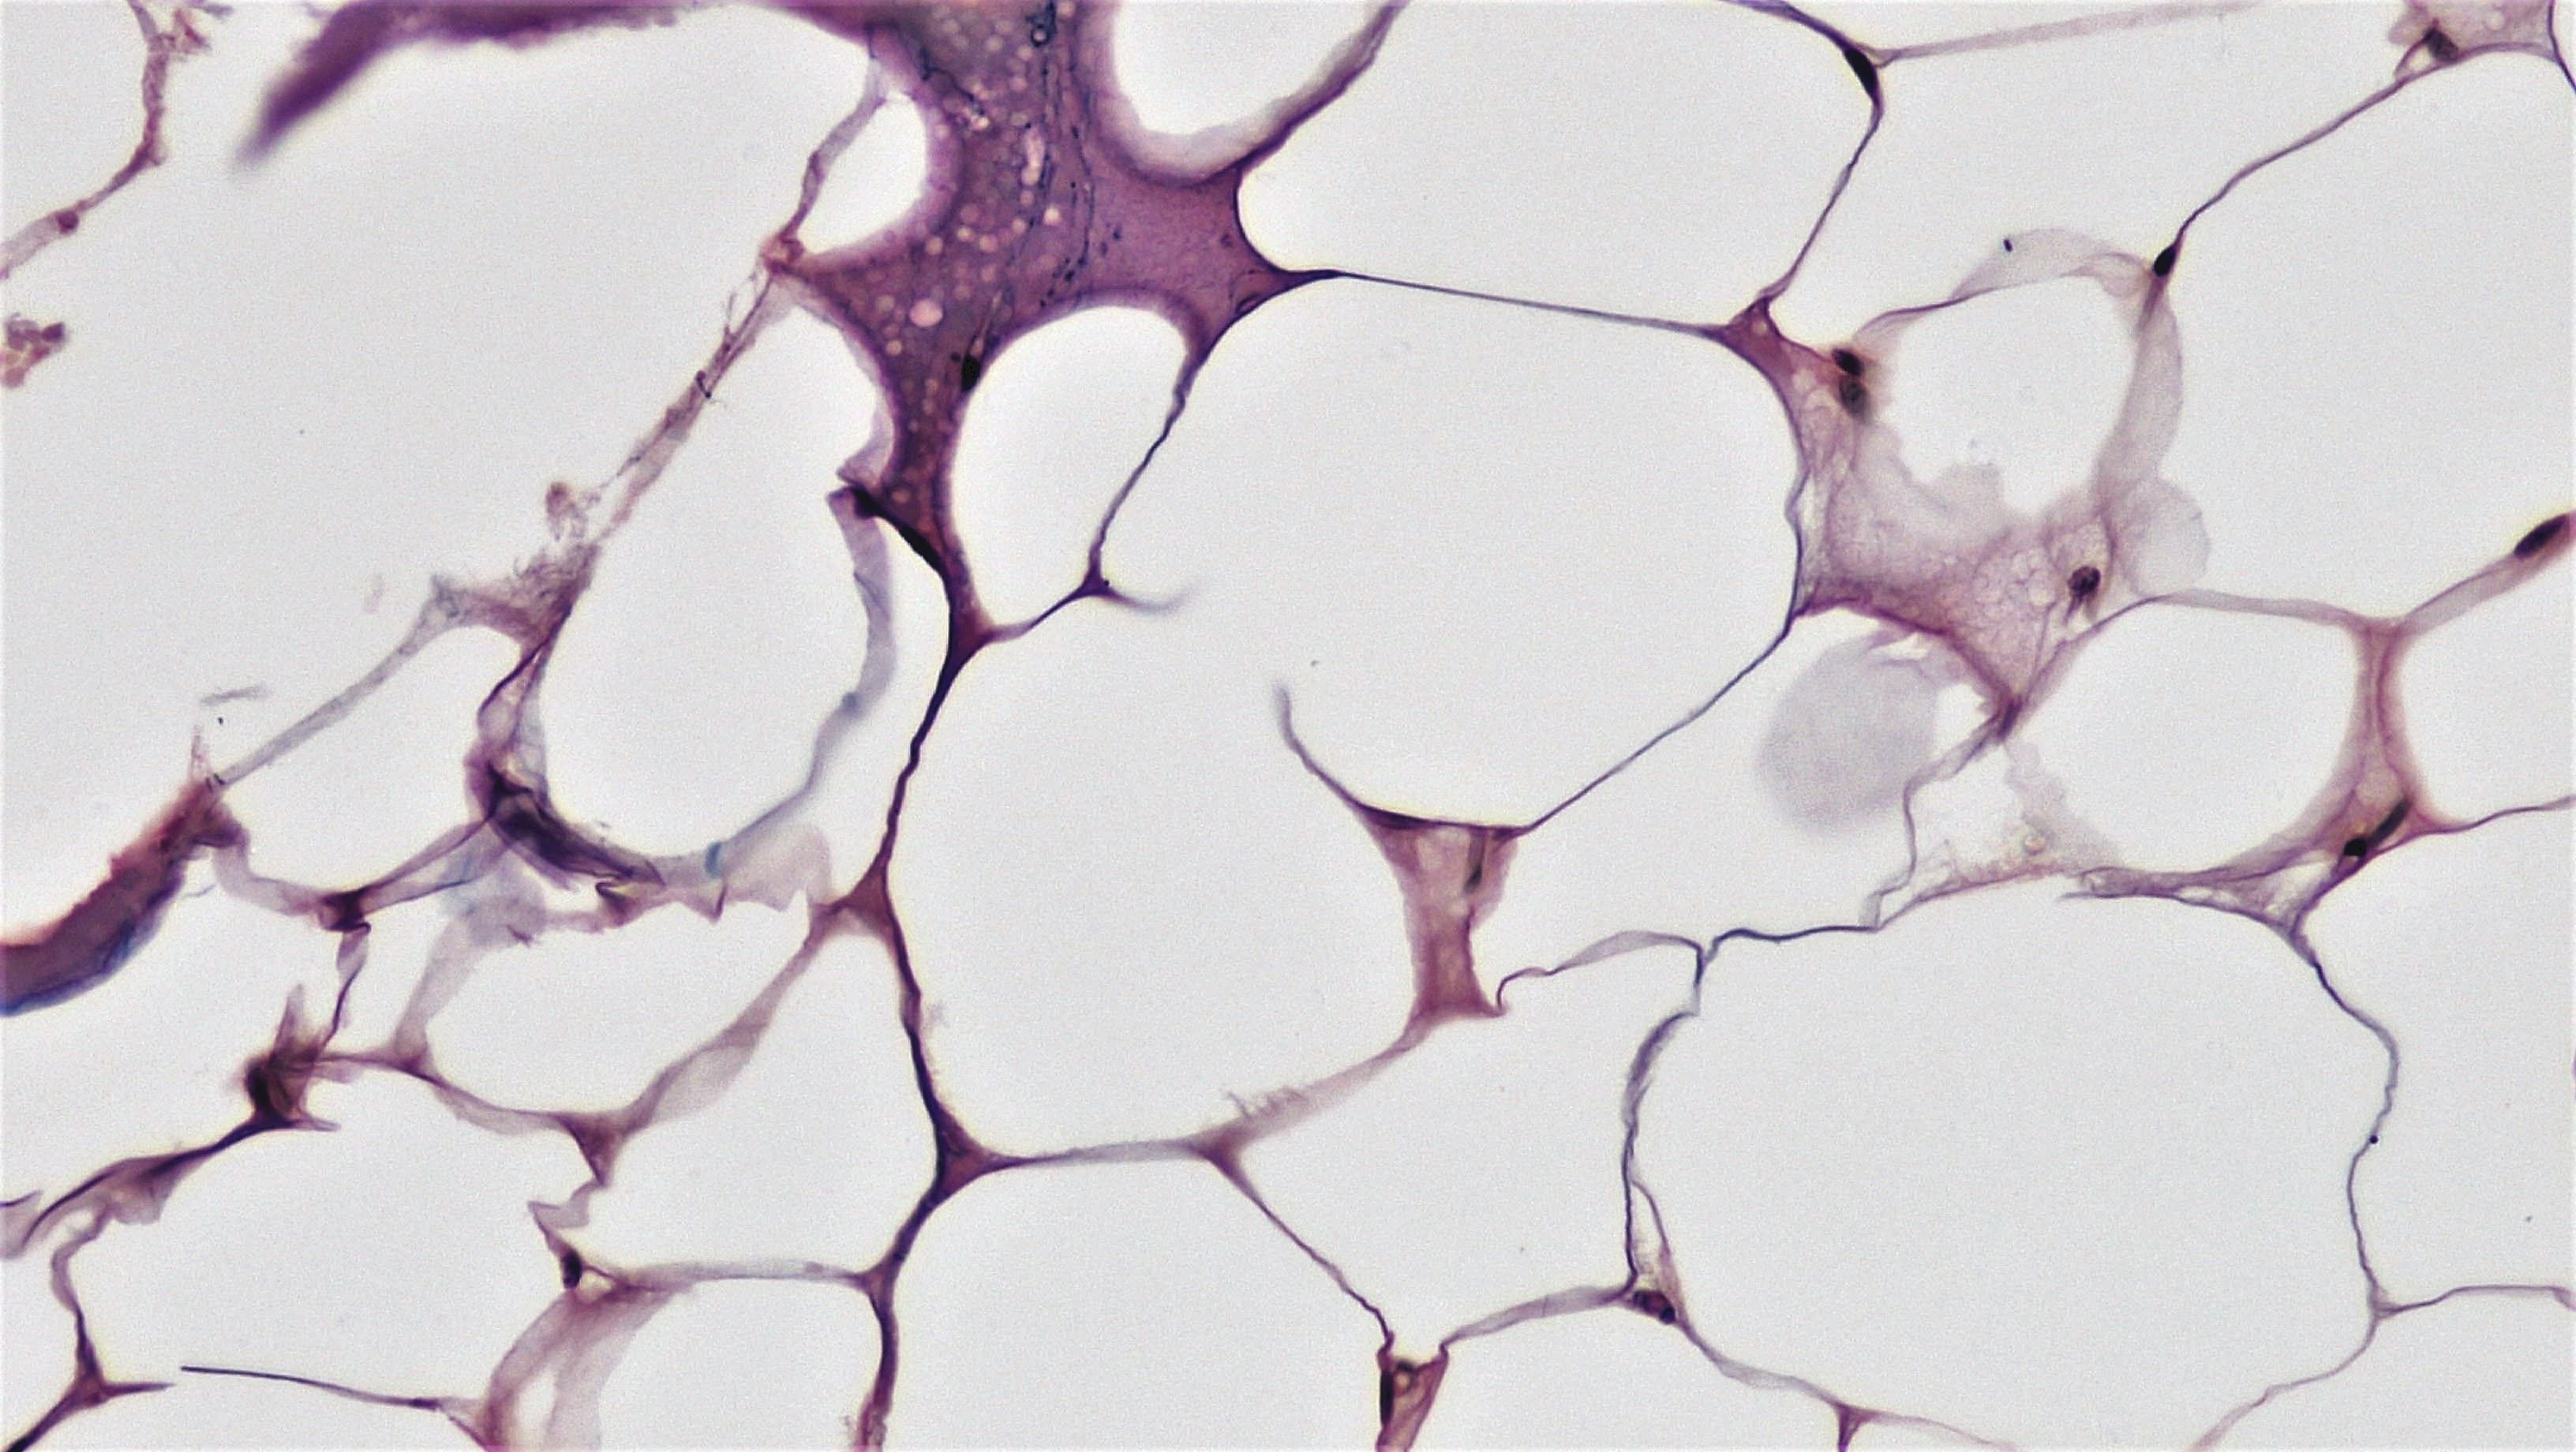

Un team internazionale ha appena pubblicato sul American Journal of Clinical Nutrition un risultato che potremmo definire storico: un’integrazione quotidiana con 2000 UI di Vitamina D ha mostrato per la prima volta un impatto diretto sul rallentamento dell’accorciamento dei telomeri, i “cappucci” protettivi dei nostri cromosomi, oggi considerati uno dei più precisi indicatori dell’età biologica.

In parole semplici? La Vitamina D potrebbe contribuire concretamente a rallentare i meccanismi cellulari dell’invecchiamento. Aggiungiamo poi il supporto degli Omega-3, meno efficaci sui telomeri nello studio specifico, ma fondamentali nel modulare l’infiammazione e nel proteggere il sistema cardiovascolare, e abbiamo tra le mani una combinazione che promette molto più che benessere: promette un futuro più lungo e in salute.